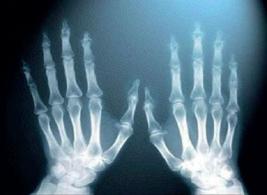

Біологія + Фізика Цікаво, що рентгенівське випромінювання називають ще пулюївським на честь українського фізика Івана Пулюя (1845–1918), який уперше застосував і дослідив їх ще в 1892 році. Які особливості природи людини?

Кістки скелета людини відрізняються між собою за формою, розмірами, будовою, хімічним складом тощо. Навіть одні й ті самі кістки у скелетах різних людей можуть відрізнятися (наприклад, тазові кістки чоловіка і жінки різного розміру). Змінюються кістки і з віком людини. У молодому віці вони містять значно більше осеїну, а в людей похилого віку в кістках уже більше неорганічних речовин.